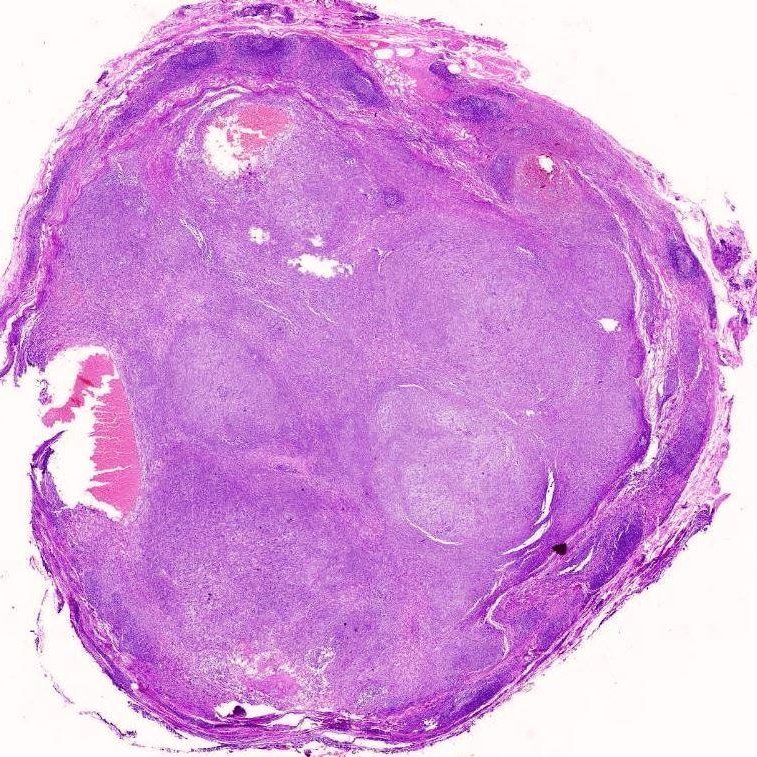

#PathQuiz 🔬 A) Alveolar Rhabdomyosarcoma B) Proximal Epithelioid Sarcoma C) Clear cell sarcoma D) Extrarenal Rhabdoid Tumor #Pathology #SoftTissuePath #PediPath👶 Clue in caption 🧐

#PathQuiz 🔬

A) Alveolar Rhabdomyosarcoma

B) Proximal Epithelioid Sarcoma

C) Clear cell sarcoma

D) Extrarenal Rhabdoid Tumor